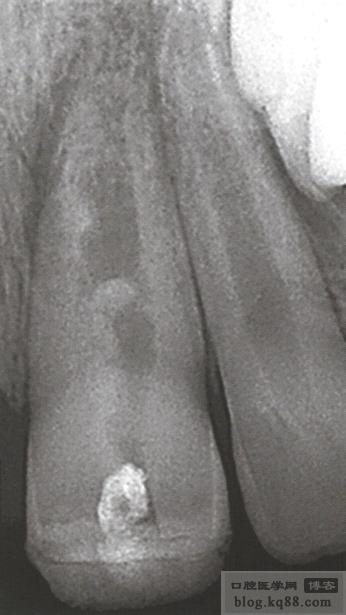

根尖孔未發(fā)育完成,根尖孔粗大或出血的病例 如果直接根充,即使充填效果看上去很好也可能會失敗。